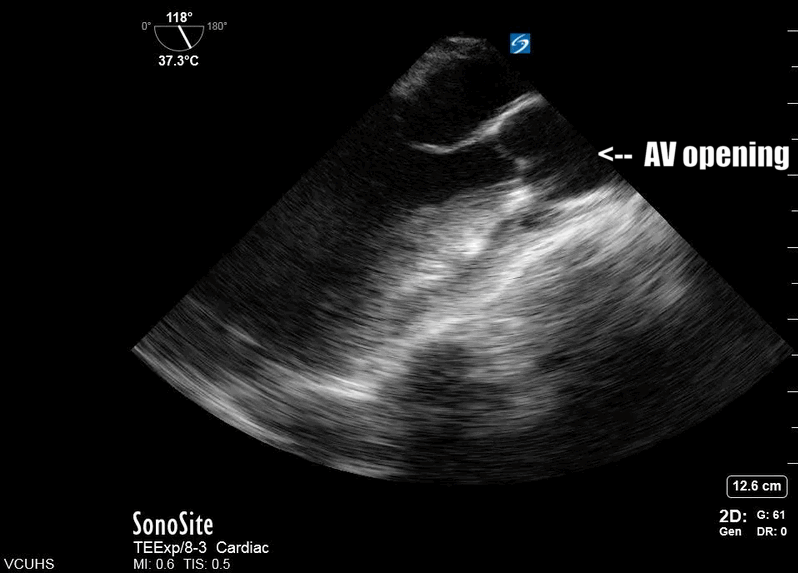

Most importantly for the resuscitationist, the ME-LAX view is used to evaluate the quality of CPR and hand placement for chest compressions; so it should be obtained during initiation of CPR and even when changing CPR providers if possible. Optimal chest compressions should result in vigorous LV squeeze with near concurrent aortic valve opening (Figure 2). Incorrect compressions, usually too high on the chest wall, will result in LV outflow obstruction and ineffective CPR (Figure 3). This can be seen on the ME-LAX view as squeeze over the AV itself, narrowing of the aortic outflow tract, absence of LV compression and/or absence of aortic valve opening during compressions. Signs of ineffective CPR should prompt adjustments in compression location and/or depth and subsequent re-evaluation for effectiveness.2

Figure 2. Me-LAX view during CPR (slowed to 50% speed) showing mid-LV compression with concurrent aortic valve opening

Figure 3: ME-LAX view during CPR (slowed to 50% speed) showing complete compression of the aortic root during CPR